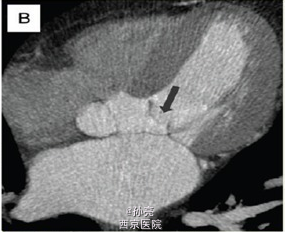

48 岁男性患者,4 年前因梗阻型肥厚性心肌病曾于我院医疗中心行室间隔无水酒精消融术。尽管术后使用β受体阻滞剂、异搏定和丙吡胺,患者仍有劳力性呼吸困难症状出现。 结合既往心脏 CT 片对照,未发现有意义的冠状动脉病变。室间隔壁为 12mm 厚。更进一步,我们观察到收缩期时二尖瓣有一个不同寻常的组织突出于左室流出道(图 1B)。 这种机械方面的梗阻我们再次用经胸壁超声得以证实,当多余的组织靠近室间隔时,该组织与最大收缩期左室流出道的压力阶差为 80mmHg(图 1B)。 心脏 MRI 再次确认出现的二尖瓣附件组织阻塞左室流出道,加速了收缩期的血液流动(图 1C)